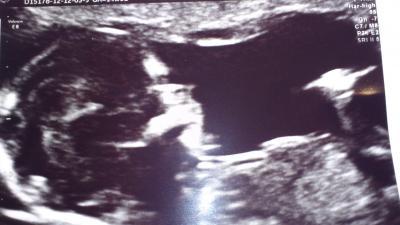

Hallo ihr lieben, Ich war heute mit meinem Puschelchen beim FA... Alles Gesund und Munter, hat sich.schön bewegt, hat schön geschlagen, es hat getrunken, die arme gestreckt ..... Und die.FA hat uns sogar zu 85% mitgeteilt das eine Prinzessin wird. Mein Mann war mit bei und freut sich riesig... Neuer ET Termin 2.8.13 Baby ist schon etwas weiter :-) Anbei ein Foto. LG Dani und Puschel

Bild zu Fa Bericht mit 85% Outing :-) - Forum für August - Mamis